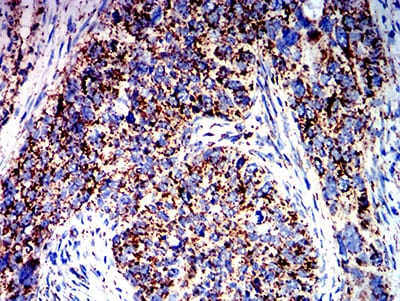

Immunohistochemical analysis of paraffin-embedded human lung cancer tissues using ATPIF1 mouse mAb with DAB staining.

-

Immunohistochemical analysis of paraffin-embedded human cervical cancer tissues using ATPIF1 mouse mAb with DAB staining.